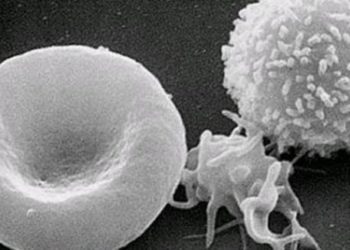

The Scan by 2 Minute Medicine®: Patient Zero: Immunotherapy for Brain Tumors?, Over-the-Counter Birth Control, Florida Supreme Court Deals a Devastating Blow to Abortion Access, Schwarzenegger’s Post-Pacemaker Update on Instagram